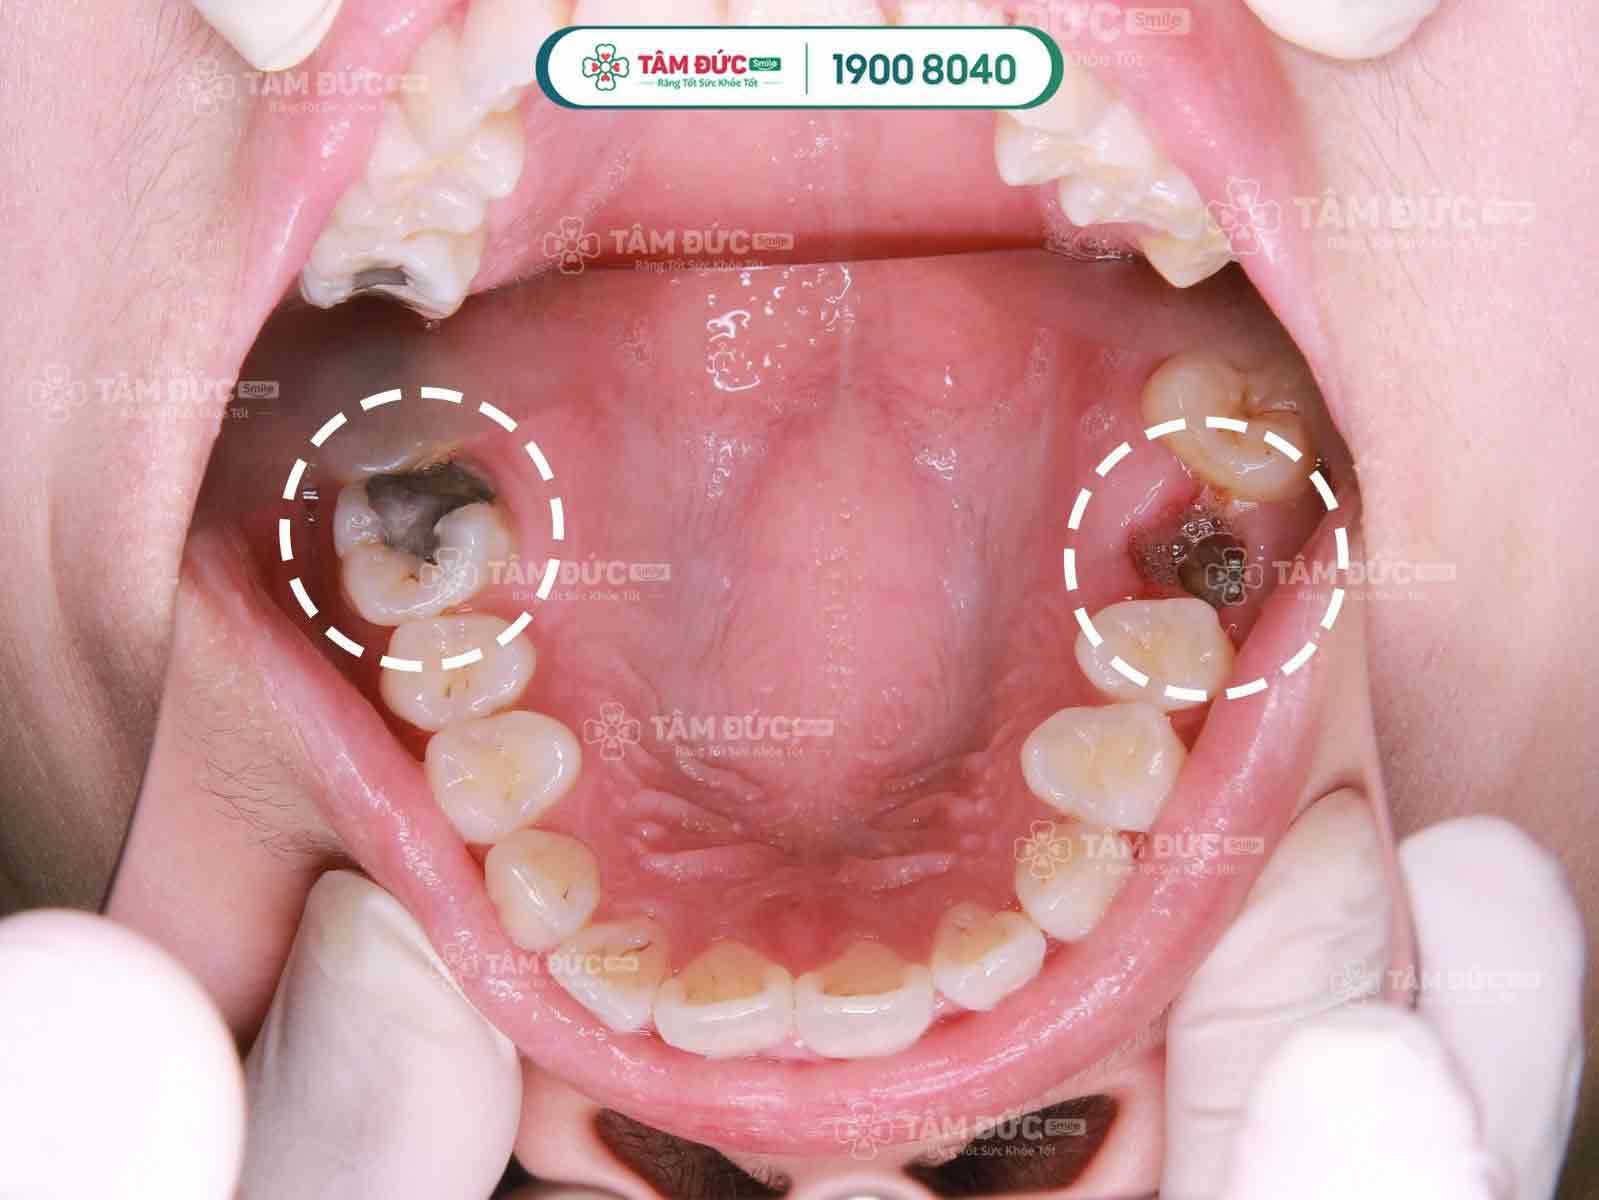

Răng bị sâu ăn mòn hết gây ảnh hưởng chức năng ăn uống

Răng bị sâu ăn mòn hết và bị hoại tử tuỷ thì không nên giữ lại